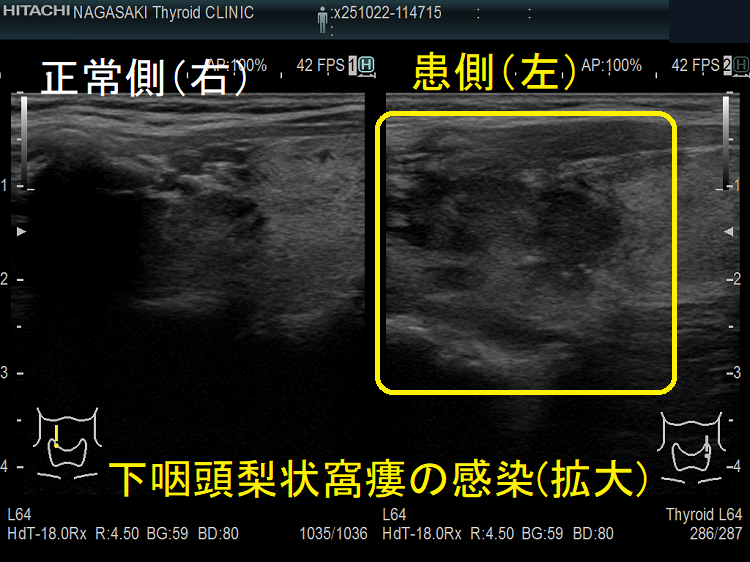

急性化膿性甲状腺炎に至らない下咽頭梨状窩瘻の感染もあります。下咽頭梨状窩瘻が甲状腺内でなく、甲状腺周囲に開口している場合に起こります。

- 超音波検査(エコー検査)で、甲状腺内~甲状腺外の周辺組織に続く境界不明瞭な低エコー領域を認めます。

甲状腺外の低エコー領域があれば、診断は容易ですが、初期は甲状腺内に限局した低エコー領域なので亜急性甲状腺炎との鑑別が難しい。筆者の経験では、どちらの低エコー領域も内部不均一になりますが、亜急性甲状腺炎の低エコー領域は境界不明瞭で飛び石状ですが、急性化膿性甲状腺炎の低エコー領域は単発性・連続性で、比較的境界不明瞭が多い。

①甲状腺内の低エコー領域は片側性が多い(特に下咽頭梨状窩瘻は左側)。甲状腺悪性リンパ腫のような入道雲様の事も。

②甲状腺外の低エコー領域は滲出液・膿瘍で、頭内側に多い